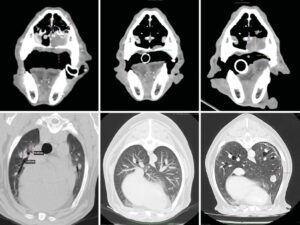

Revisión de patologías adrenales en diagnóstico por imagen

La alteración de las secreciones hormonales y los procesos tumorales son las patologías más frecuentes de las glándulas adrenales. La radiografía, la ecografía y las técnicas de imagen avanzadas, junto con las laboratoriales, son herramientas clave para su diagnóstico.